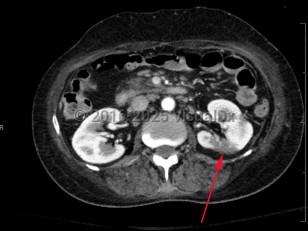

Renal infarction

Renal infarction is felt to be a rare condition with incidence varying based on study: 1.4% in autopsy studies and 0.007% based on emergency department data. However, it is also an underrecognized condition and often missed.

Symptoms often mimic other renal pathology, including acute onset of flank pain or abdominal pain, hematuria, and occasionally fever or vomiting; thus, diagnosis can be delayed. Physical examination findings include acute hypertension and, rarely, other signs of extrarenal embolization, including focal neurologic deficits.